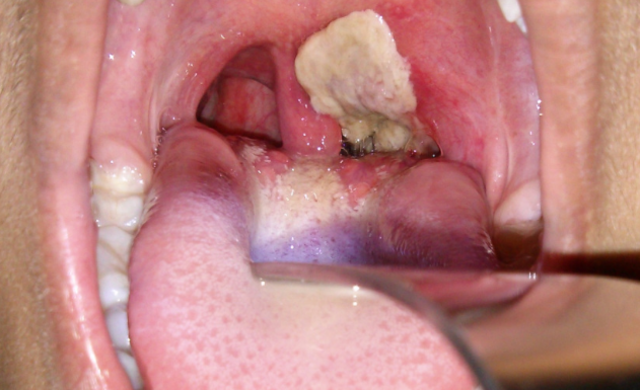

Diphtheria

Diphtheria is a serious bacterial infection that usually affected the mucous membranes of the nose and throat. The symptoms of Diphtheria were very harsh sore throats, harsh coughs, moderate to severe fever, weakness, and bull-neck swelling/swollen glands. The first pandemic broke out during the 1850-1860 decade. During the breakout over 5,000 people died from this disease. It was very dangerous and lead to many unnecessary deaths because they was not cure discovered yet.